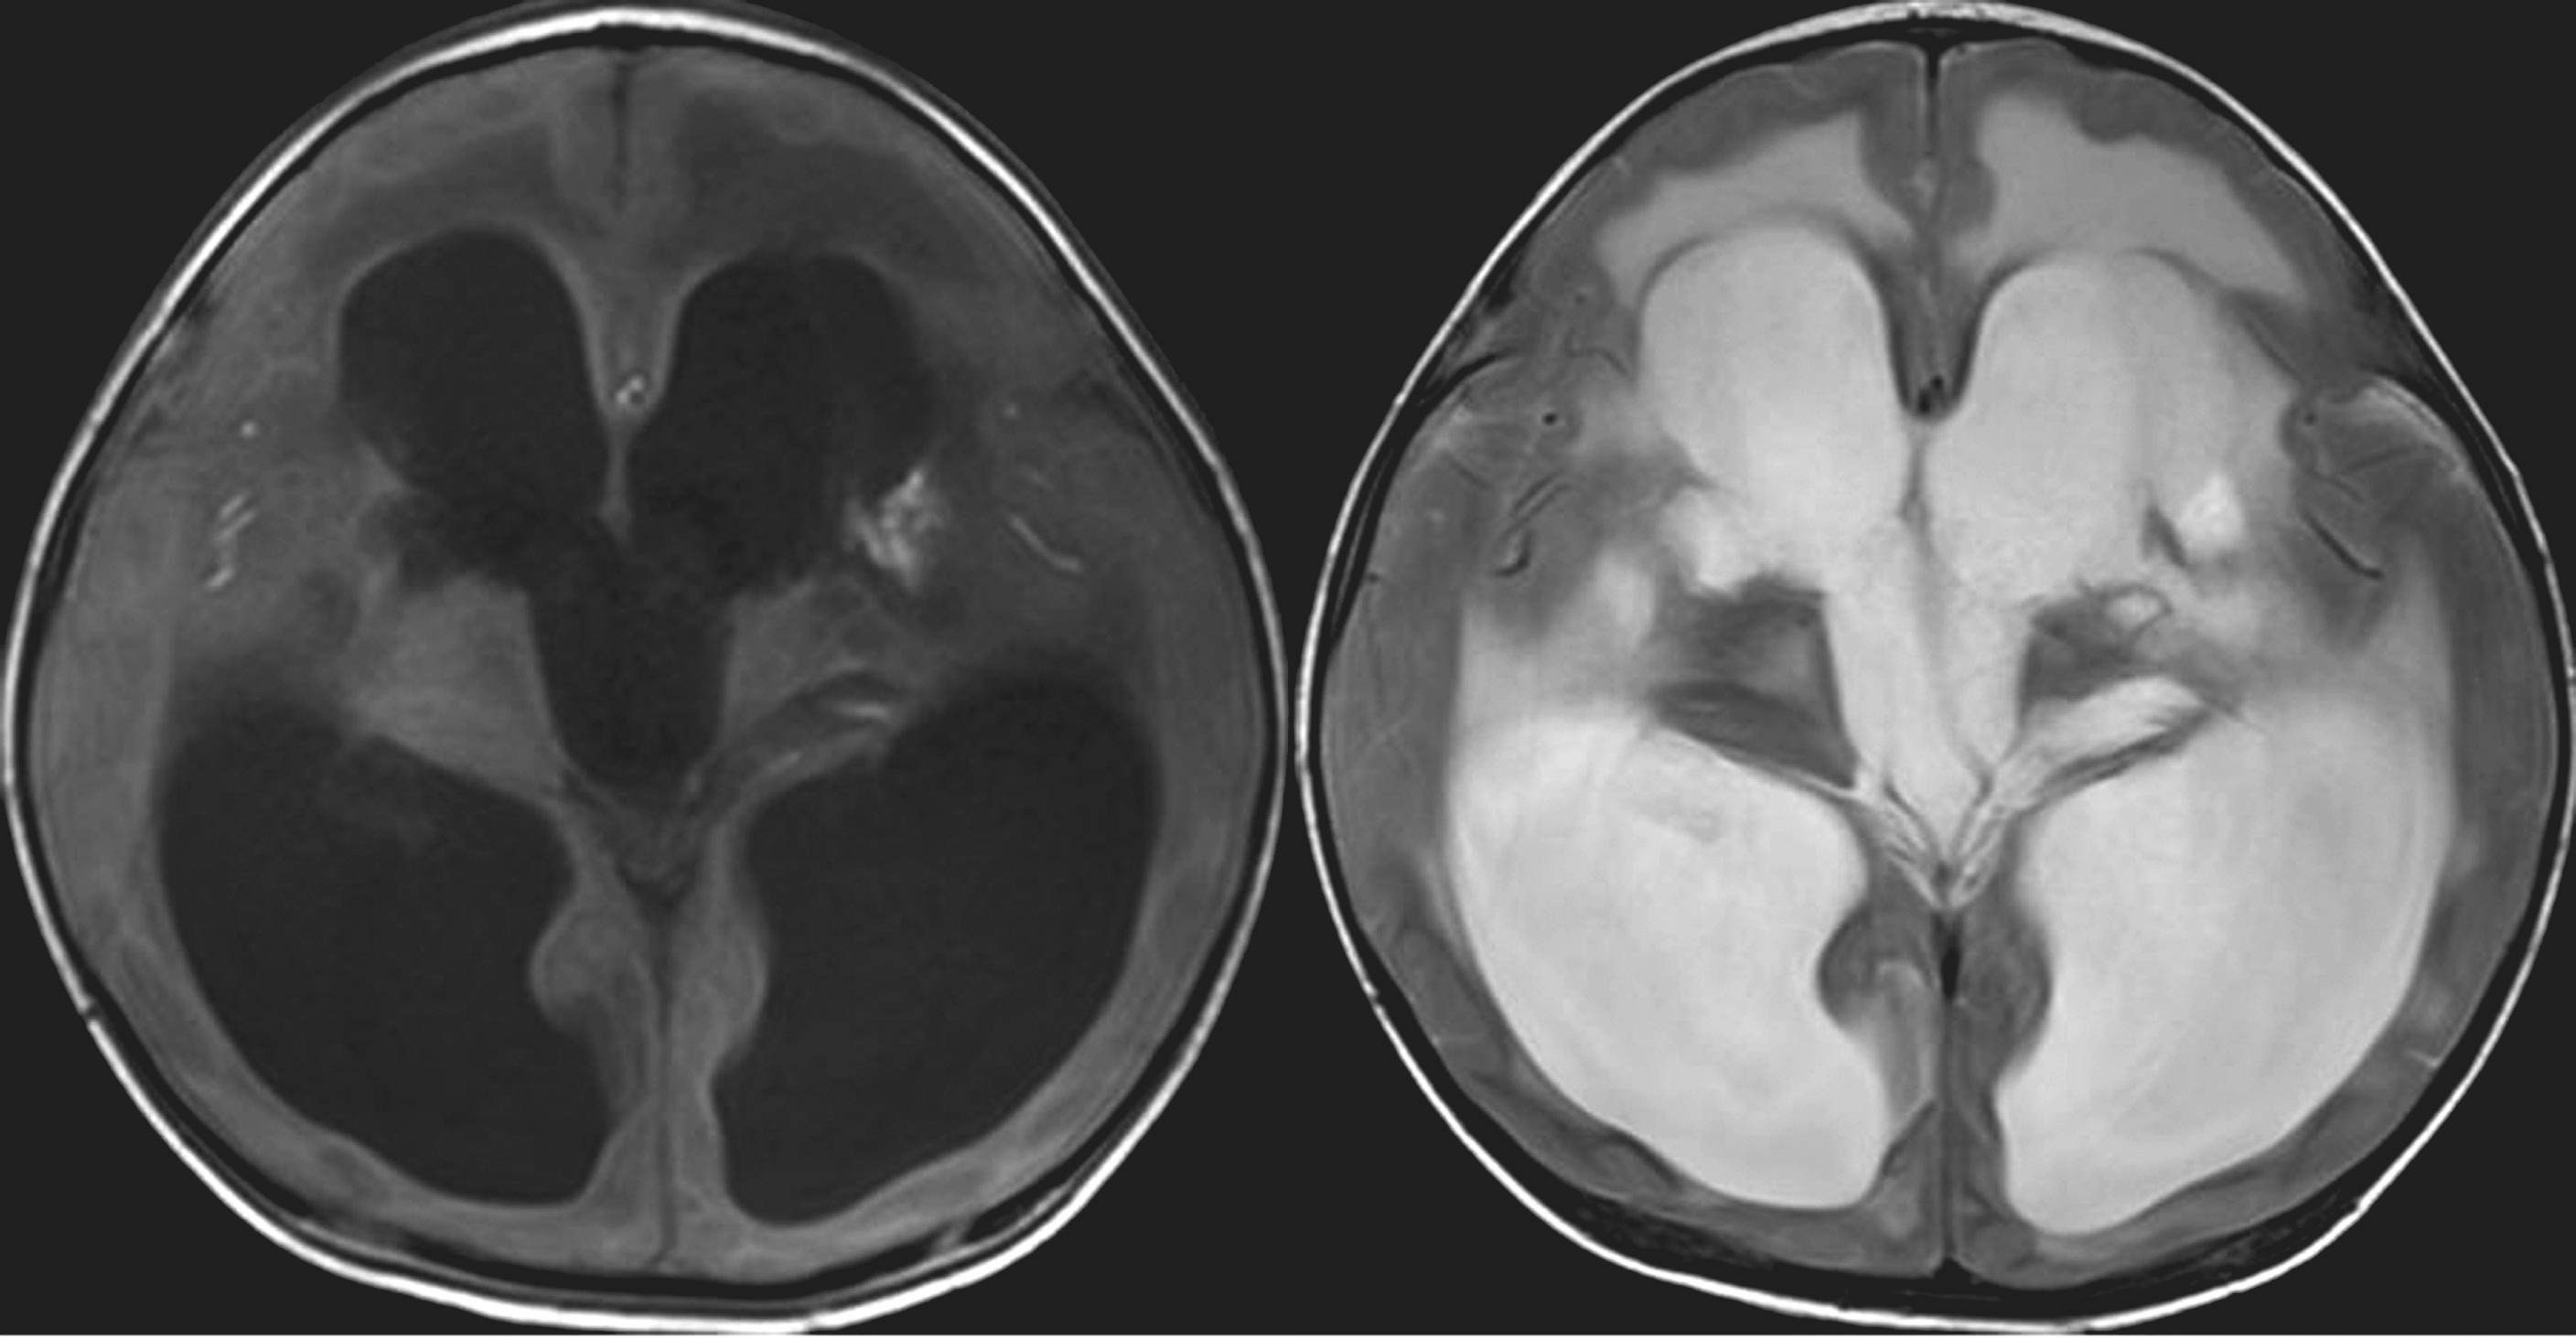

(1)CT表现(图5-1-1):

①脑室系统普遍扩大而蛛网膜下腔变浅或消失;②侧脑室额角和颞角变钝、变圆,枕角扩大出现较晚;③侧脑室周围白质内可见明显的低密度水肿带。

图5-1-1 高压力性脑积水的CT表现

(2)MRI表现(图5-1-2):

①脑室系统明显扩大,蛛网膜下腔消失;②脑室额角和/或颞角呈圆形,伴脑室周围呈低或等T 1 信号、高T 2 信号的间质性水肿带;③第三脑室呈球形扩大,视隐窝和漏斗隐窝变浅变钝;④胼胝体位置抬高。

图5-1-2 高压力性脑积水的MRI表现